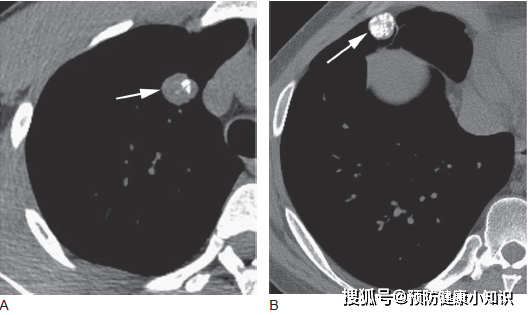

如果肺部曾經發生過炎症或者損傷,那就可能到至鈣化,因為壞死的組織需要自我修復,在修復的過程中形成鈣化。最常見的肺內鈣化是由於肺結核的感染導致的,所以可能有些人在檢查時,醫生會詢問是否以前得過肺結核。當然,還有肺炎等其實疾病也會導致鈣化。

正常情况下,肺部鈣化也不需要手術,但如果其存在於0. 8釐米以上的肺結節中或者在肺部腫塊中,那就需要及時的詢問醫生。

此外,在肺部的淋巴結中也能看到鈣化,這一般也是由於結核的感染或者組織的修復導致的,不需要過度的擔心。